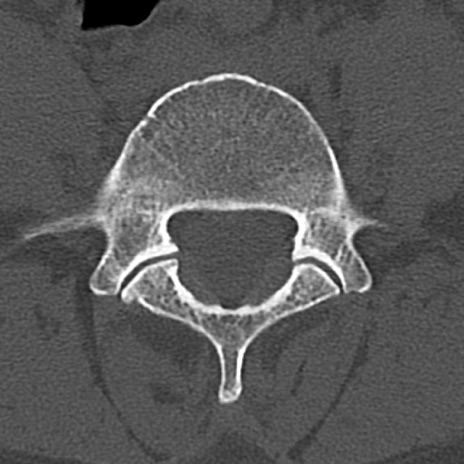

腰椎CT

横断像と矢状断像